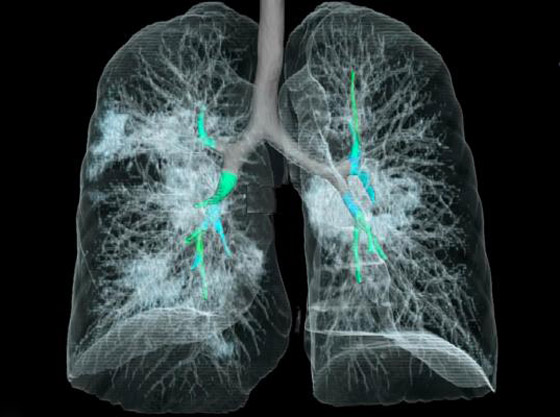

تصوير مقطعي محوسب من مستشفى جامعة جورج واشنطن يُظهر آثار فيروس كورونا المستجد، أو ما يُعرف بـ"كوفيد-19" رئتي رجل عمره 59 عاماً. فشاهدوا معنا في الفيديو المدهش أدناه كيف تبدو رئة مصاب بفيروس كورونا (فيروس كوفيد 19) وما يحصل داخلها..